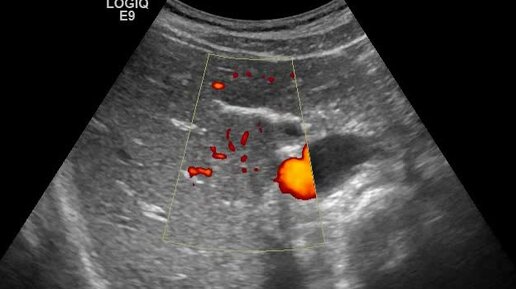

Очаговая узловая гиперплазия печени. Наблюдение №2. Допплерография

Ультразвуковые находки от врача УЗД Зорина Я.П.